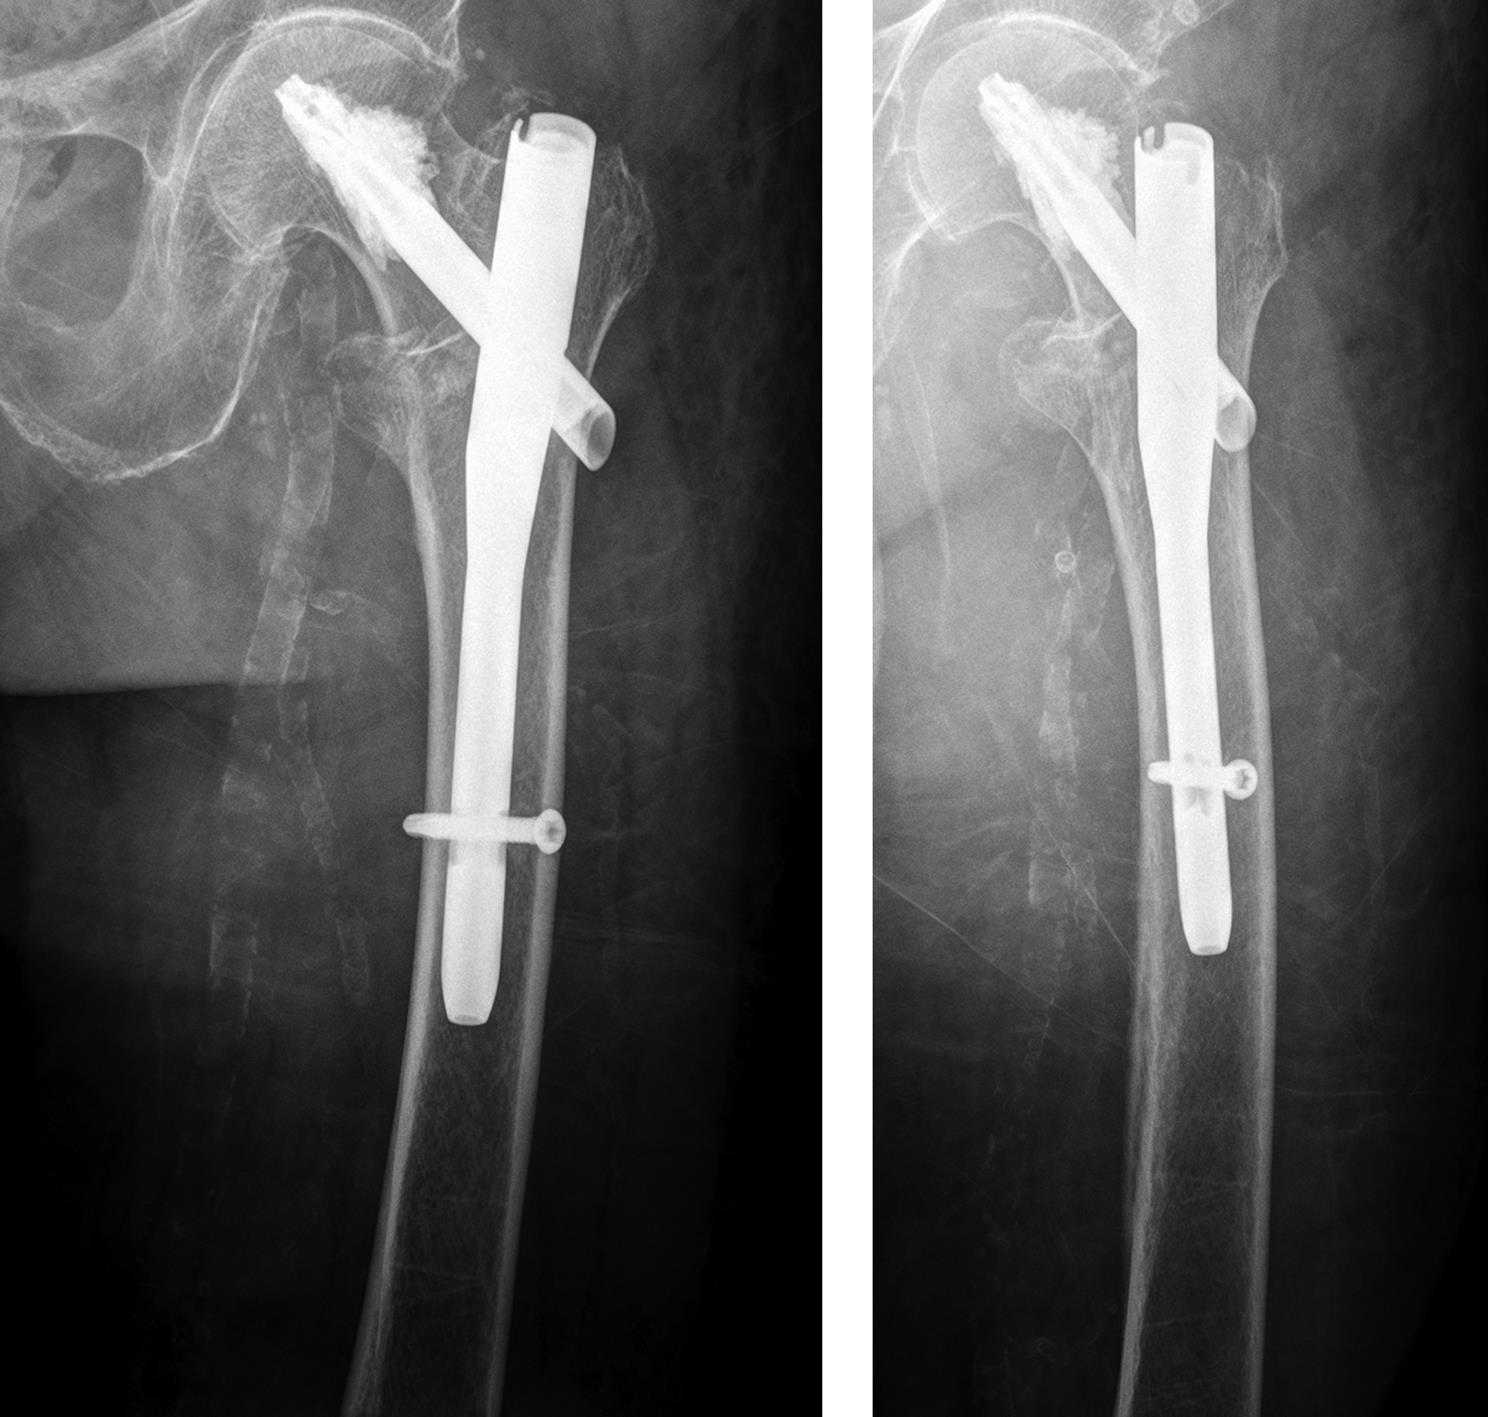

An 83-year-old female patient sustained a 31-A.2.2 fracture of the right proximal femur after a fall at home (Figs 1-2). Intraoperative and postoperative images are shown (Figs 3-5).

Case provided by Michael Blauth, Innsbruck, Austria